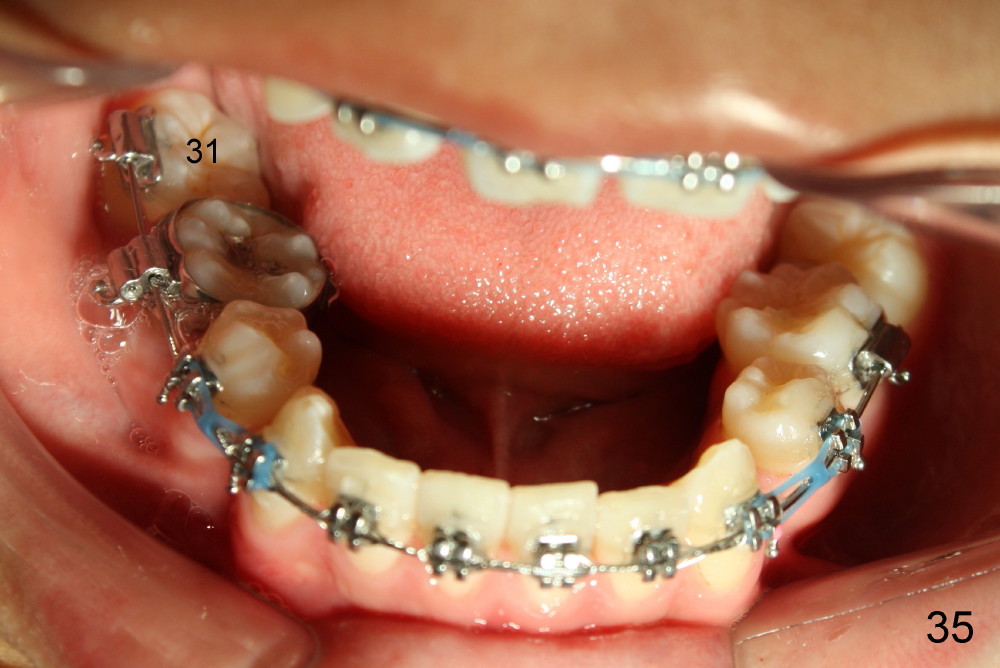

Prior to bracketing, the mesiodistal space for #18 is planned to be obtained by moving #20 and then #19 mesially (Fig.31-35, 16x16 ss). The six anterior lower teeth are tied together in a figure 8 fashion. Power chains are placed between the lower canine and the 2nd bicuspids. The upper diastemata are to be closed by power chains between the 1st molars.